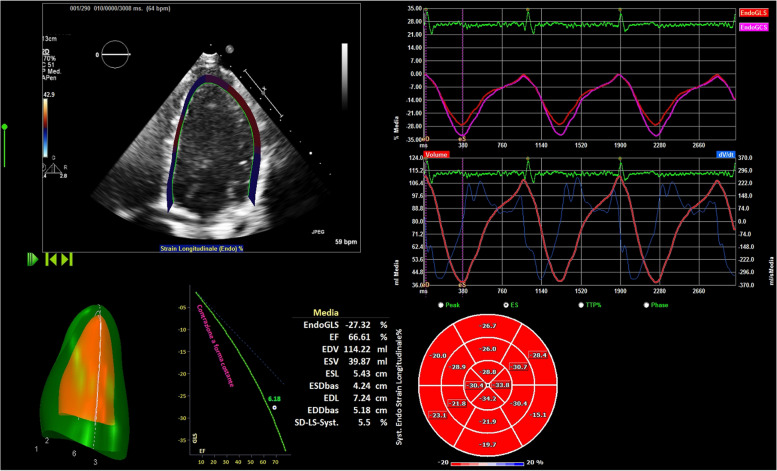

Methods: 21 female elite athletes (23.2 ± 5.3 years), 25 women with twin pregnancies (35.4 ± 5.7 years) and 25 healthy competitive female athletes (controls), age-matched with pregnant women (34.9 ± 7.9 years), were enrolled. This latter group was included to minimize the effect of age on cardiac remodeling. All women evaluated through anamnestic collection, physical examination, 12 leads ECG, standard echocardiogram and strain analysis. Sphericity (SI) and apical conicity (ACI) indexes were also calculated.

Results: Pregnant women showed higher LA dimension (p < 0.001) compared to both groups of athletes. LV e RV GLS were significantly different in pregnant women compared to female athletes (p = 0.02 and 0.03, respectively). RV GLS was also different between pregnant women and controls (p = 0.02). Pregnant women showed significantly higher S' wave compared to female athletes (p = 0.02) but not controls. Parameters of diastolic function were significantly higher in athletes (p = 0.08 for IVRT and p < 0.001 for E/A,). SI was lower in athletes in both diastole (p = 0.01) and systole (p < 0.001), while ACIs was lower in pregnant women (p = 0.04).

Conclusions: Cardiac remodeling of athletes and pregnant women could be similar at first sight but different in LV shape and in GLS, highlighting a profound difference in longitudinal deformation between athletes and pregnant women. This difference seems not to be related with age. These findings suggest that an initial maternal cardiovascular maladaptation could occur in the third trimester of twin pregnancies.